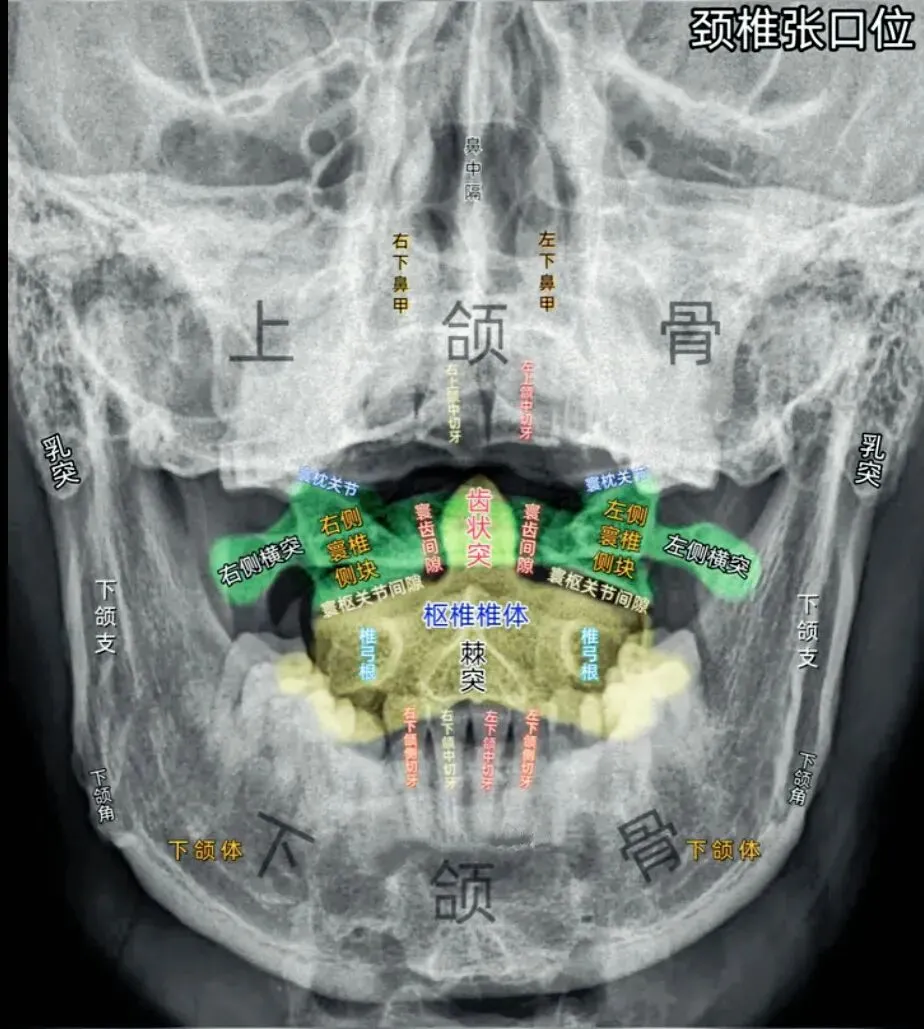

十张口是指寰枢椎的结构和位置关系,我们主要观察寰齿间隙和寰枢关节间隙及寰椎侧块的大小,来判断寰枢关节有无脱位的情况。

首先是寰齿间隙,如果枢椎与颈三的棘突位于同一条直线,

那么寰齿间隙哪边宽,就代表寰椎向哪边发生了侧方移位。

如果不在一条直线上,那就代表枢椎也有侧向的移动或旋转。

接下来是寰枢关节间隙,也称寰枢外侧关节,主要看两侧间隙是否等大,

如果一边宽一边窄,就代表寰椎向窄的一方发生了侧向倾斜。

再下来看寰椎侧块的大小,正常情况下侧块两边的宽度是等大的,

如果哪边侧块变大,就代表哪边的侧块向前方发生了旋转。